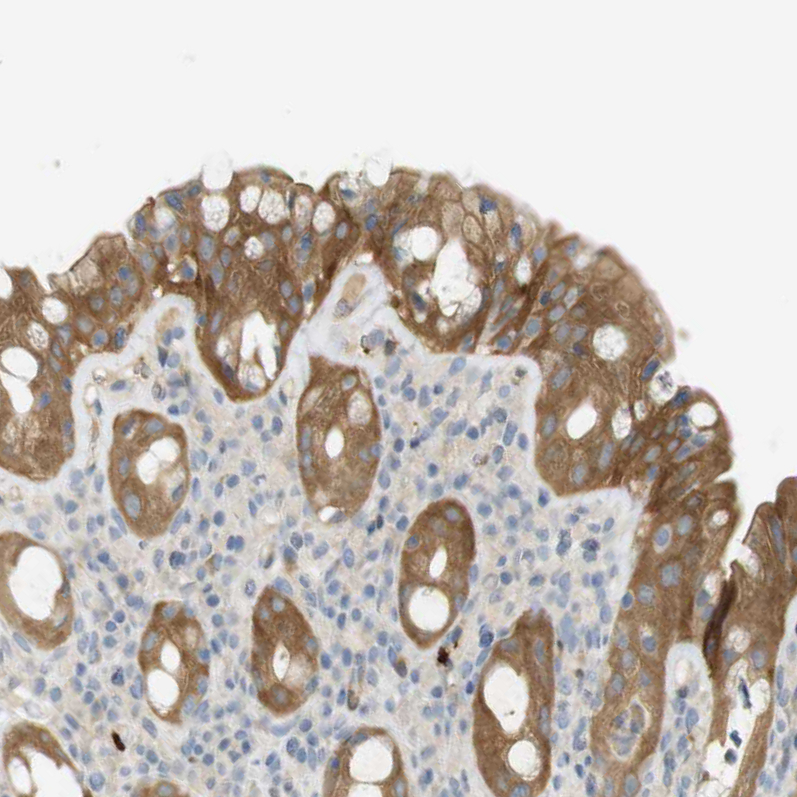

Immunohistochemical staining of human heart muscle shows moderate cytoplasmic positivity in cardiomyocytes.